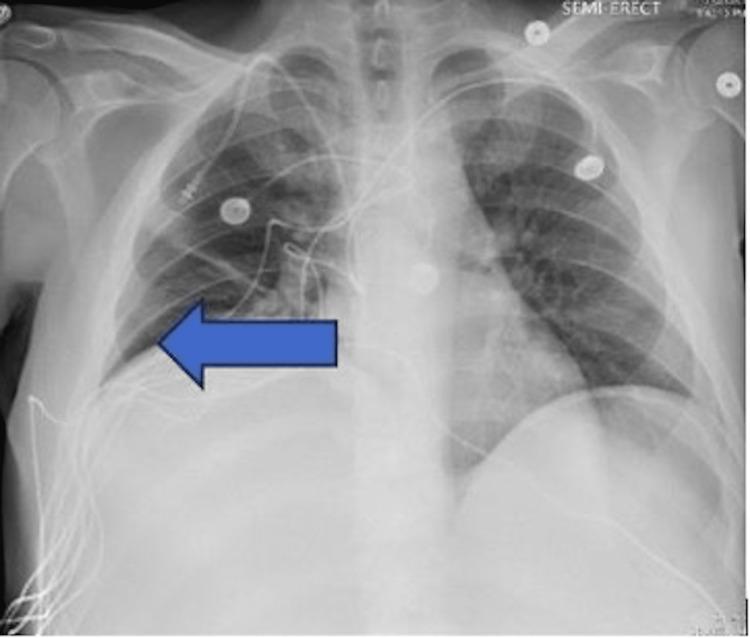

Lactic acidosis occurs from an overproduction of lactate or decreased metabolism. It is common in critically ill patients, especially those with hematological conditions such as multiple myeloma, leukemia, and lymphoma. There are two types of lactic acidosis, Type A and Type B, with Type B presenting more commonly in hematological conditions that require prompt diagnosis and treatment of the underlying condition. We present a case of a 43-year-old male with Type B lactic acidosis secondary to stage IV colon cancer with metastasis to the liver. Initial laboratory work was significant for lactic acid of 16.52 mmol/L. Arterial blood gas (ABG) showed pH 7.26, pCO 21 mmHg, pO 111 mmHg, and HCO 9 mEq/L, revealing an anion gap and metabolic acidosis with compensatory respiratory alkalosis. Initially, the patient was treated with aggressive fluid management, IV antibiotics, and sodium bicarbonate; however, his lactic acid continued to rise. The recommendation was made for urgent dialysis. Despite treatments, the prognosis is poor.

乳酸性酸中毒是由于乳酸生成过多或代谢减少所致。在危重症患者中很常见,尤其是那些患有血液系统疾病的患者,如多发性骨髓瘤、白血病和淋巴瘤。乳酸性酸中毒有两种类型,A型和B型,B型在需要及时诊断和治疗基础疾病的血液系统疾病中更为常见。我们报告一例43岁男性,继发于IV期结肠癌伴肝转移的B型乳酸性酸中毒。初始实验室检查显示乳酸水平为16.52 mmol/L,具有显著意义。动脉血气(ABG)显示pH 7.26,pCO₂ 21 mmHg,pO₂ 111 mmHg,HCO₃⁻ 9 mEq/L,提示存在阴离子间隙和代谢性酸中毒伴代偿性呼吸性碱中毒。最初,患者接受了积极的液体管理、静脉抗生素治疗和碳酸氢钠治疗;然而,他的乳酸水平持续升高。建议进行紧急透析。尽管进行了治疗,但预后很差。